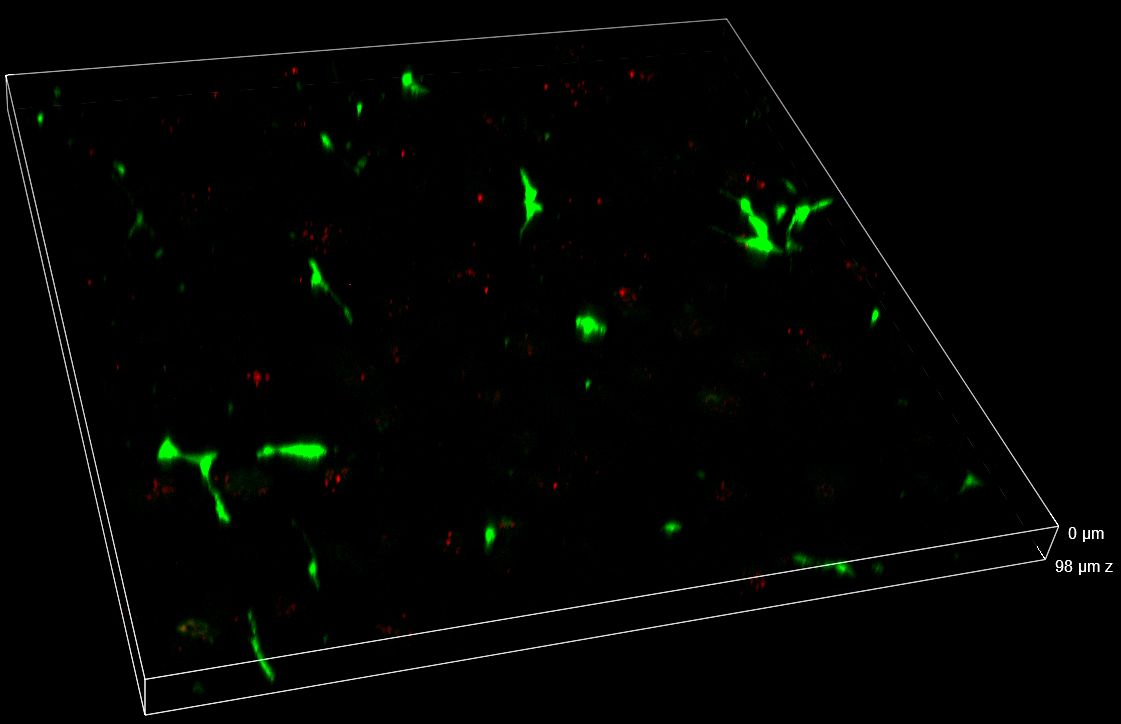

Data obtained from live monitoring of co-cultures in VITVO were compared with end-point readouts from fixed samples at specific time points post-treatment (24 and 72 h, Figure 8). 3D comparison among three different FOVs confirmed a homogeneous distribution of cells without any significant inter-field difference. These data point out that AD-MSCs TRAIL were persisted over time, instead of A673 tumor cells which massively decreased in their signal and cell density (Figure 8).

Figure 8. Z-stacks on VITVO FOVs collected and fixed at different time points with spinning disk. 3 different FOVs corresponding to 24 h and 72 h post-treatment fixed sample, respectively (10x objective magnification).